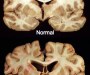

Brain Trauma’s Impact On Athletes

August 15, 2019

This may be of interest to some of you guys. Earlier today, I posted something about the late hockey player, Derek Boogaard, and his probable struggles with CTE. There has been some follow-up research done that shows CTE impacts athletes differently than the rest of the population. Any profession that runs the risk of head […]

The Dangers of Brain Trauma

Derek Boogaard was an enforcer for the Minnesota Wild and the New York Rangers of the NHL. During his career, spanning from junior hockey in Canada through his last concussion in 2010 after a fight with Matt Carkner of the Ottawa Senators, Boogaard was involved in 184 fights. The number of actual concussions that he […]